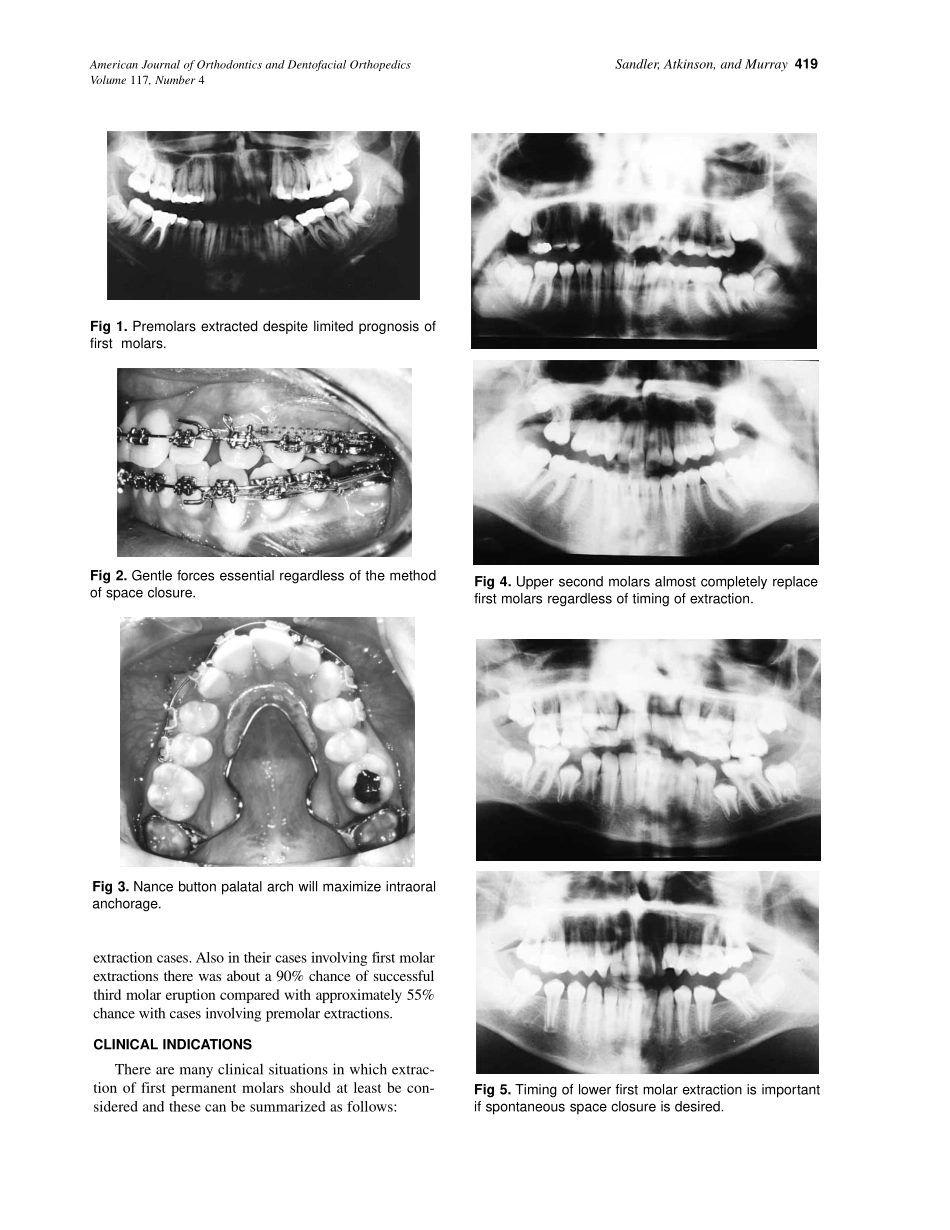

418Orthodonticcasesinvolvingtheextractionofpermanentfirstmolarsarethoughttobetechnicallymoredifficulttotreatandthatevenagoodresultisinsomewayacompromise.Manycasesthatwouldbene-fitfromthisapproachbe...